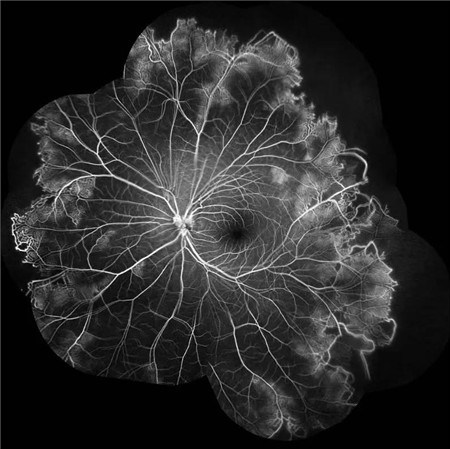

视盘附近的动脉和动脉分叉处出现瘤样动脉扩张,视盘充血,边界不清,引起视盘周围视网膜内硬性渗出;视盘周可有少量放射状出血。

静脉不规则扩张和血管鞘膜,周边部小血管广泛闭塞,交界处毛细血管扩张和异常吻合。

严重者可发生从周边到黄斑的血管闭塞和缺血、玻血、新生血管性青光眼,最终视神经萎缩。

长期追踪发现动脉瘤是一种血管炎性的游走性改变,炎症消失时,血管壁强度恢复,瘤体减小,甚至恢复正常。